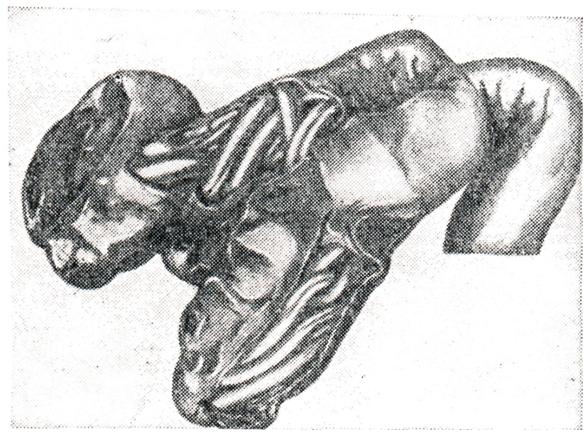

АскаридозАскаридоз (ascaridosis; греческое askaris, askaridos + - osis) — гельминтоз, вызываемый круглыми червями — аскаридами. У человека могут паразитировать несколько видов аскарид, из которых все, кроме Ascaris lumbricoides, являются облигатными паразитами животных и у человека в половозрелой стадии встречаются крайне редко. ЭтиологияВозбудитель — Ascaris lumbricoides — крупные раздельнополые гельминты (рис. 1). Размер самок 25—40 см, самцов —15—25 см. Головной конец снабжен тремя большими кутикулярными губами, окружающими ротовое отверстие. Хвостовой конец самки прямой с коническим придатком, самца — загнут на брюшную сторону. Яйца овальные (рис. 2), снабжены пятью оболочками, наружная из них толстая, фестончатая (белковой природы), прокрашивается пигментом фекалий в коричневый цвет. Встречаются яйца и без белковой оболочки. За белковой располагается трехслойная глянцевитая оболочка. Обе оболочки предохраняют зародышевую массу от механических повреждений. Внутренняя (тонкая) оболочка — липидная, полупроницаемая, задерживает соли и органические вещества, но проницаема для воды. Размер яиц 0,050-0,070 × 0,040— 0,050 мм. Аскариды могут продуцировать и так называемые неоплодотворенные яйца (яйцеклетки), имеющие неправильную форму, крупные размеры (0,050 — 0,106 × 0,040 — 0,050 мм) и лишенные зародышевой массы. Взрослые аскариды обитают в тонком отделе кишечника, где удерживаются, согнувшись дугой или свернувшись кольцом, упираясь в стенки кишки. Питаются пищевой кашицей, находящейся в кишечнике, и поверхностными слоями слизистой оболочки тонкой кишки. Самки после оплодотворения выделяют яйца на стадии одного бластомера, все развитие которых происходит в окружающей среде. Скорость развития зависит от условий температуры, влажности и состава почвы. Яйцо становится заразным после того, как сформировавшаяся в нем личинка совершит линьку и превратится в инвазионную личинку в чехлике.

Рис. 6. | ||

Рис. 7. | ||